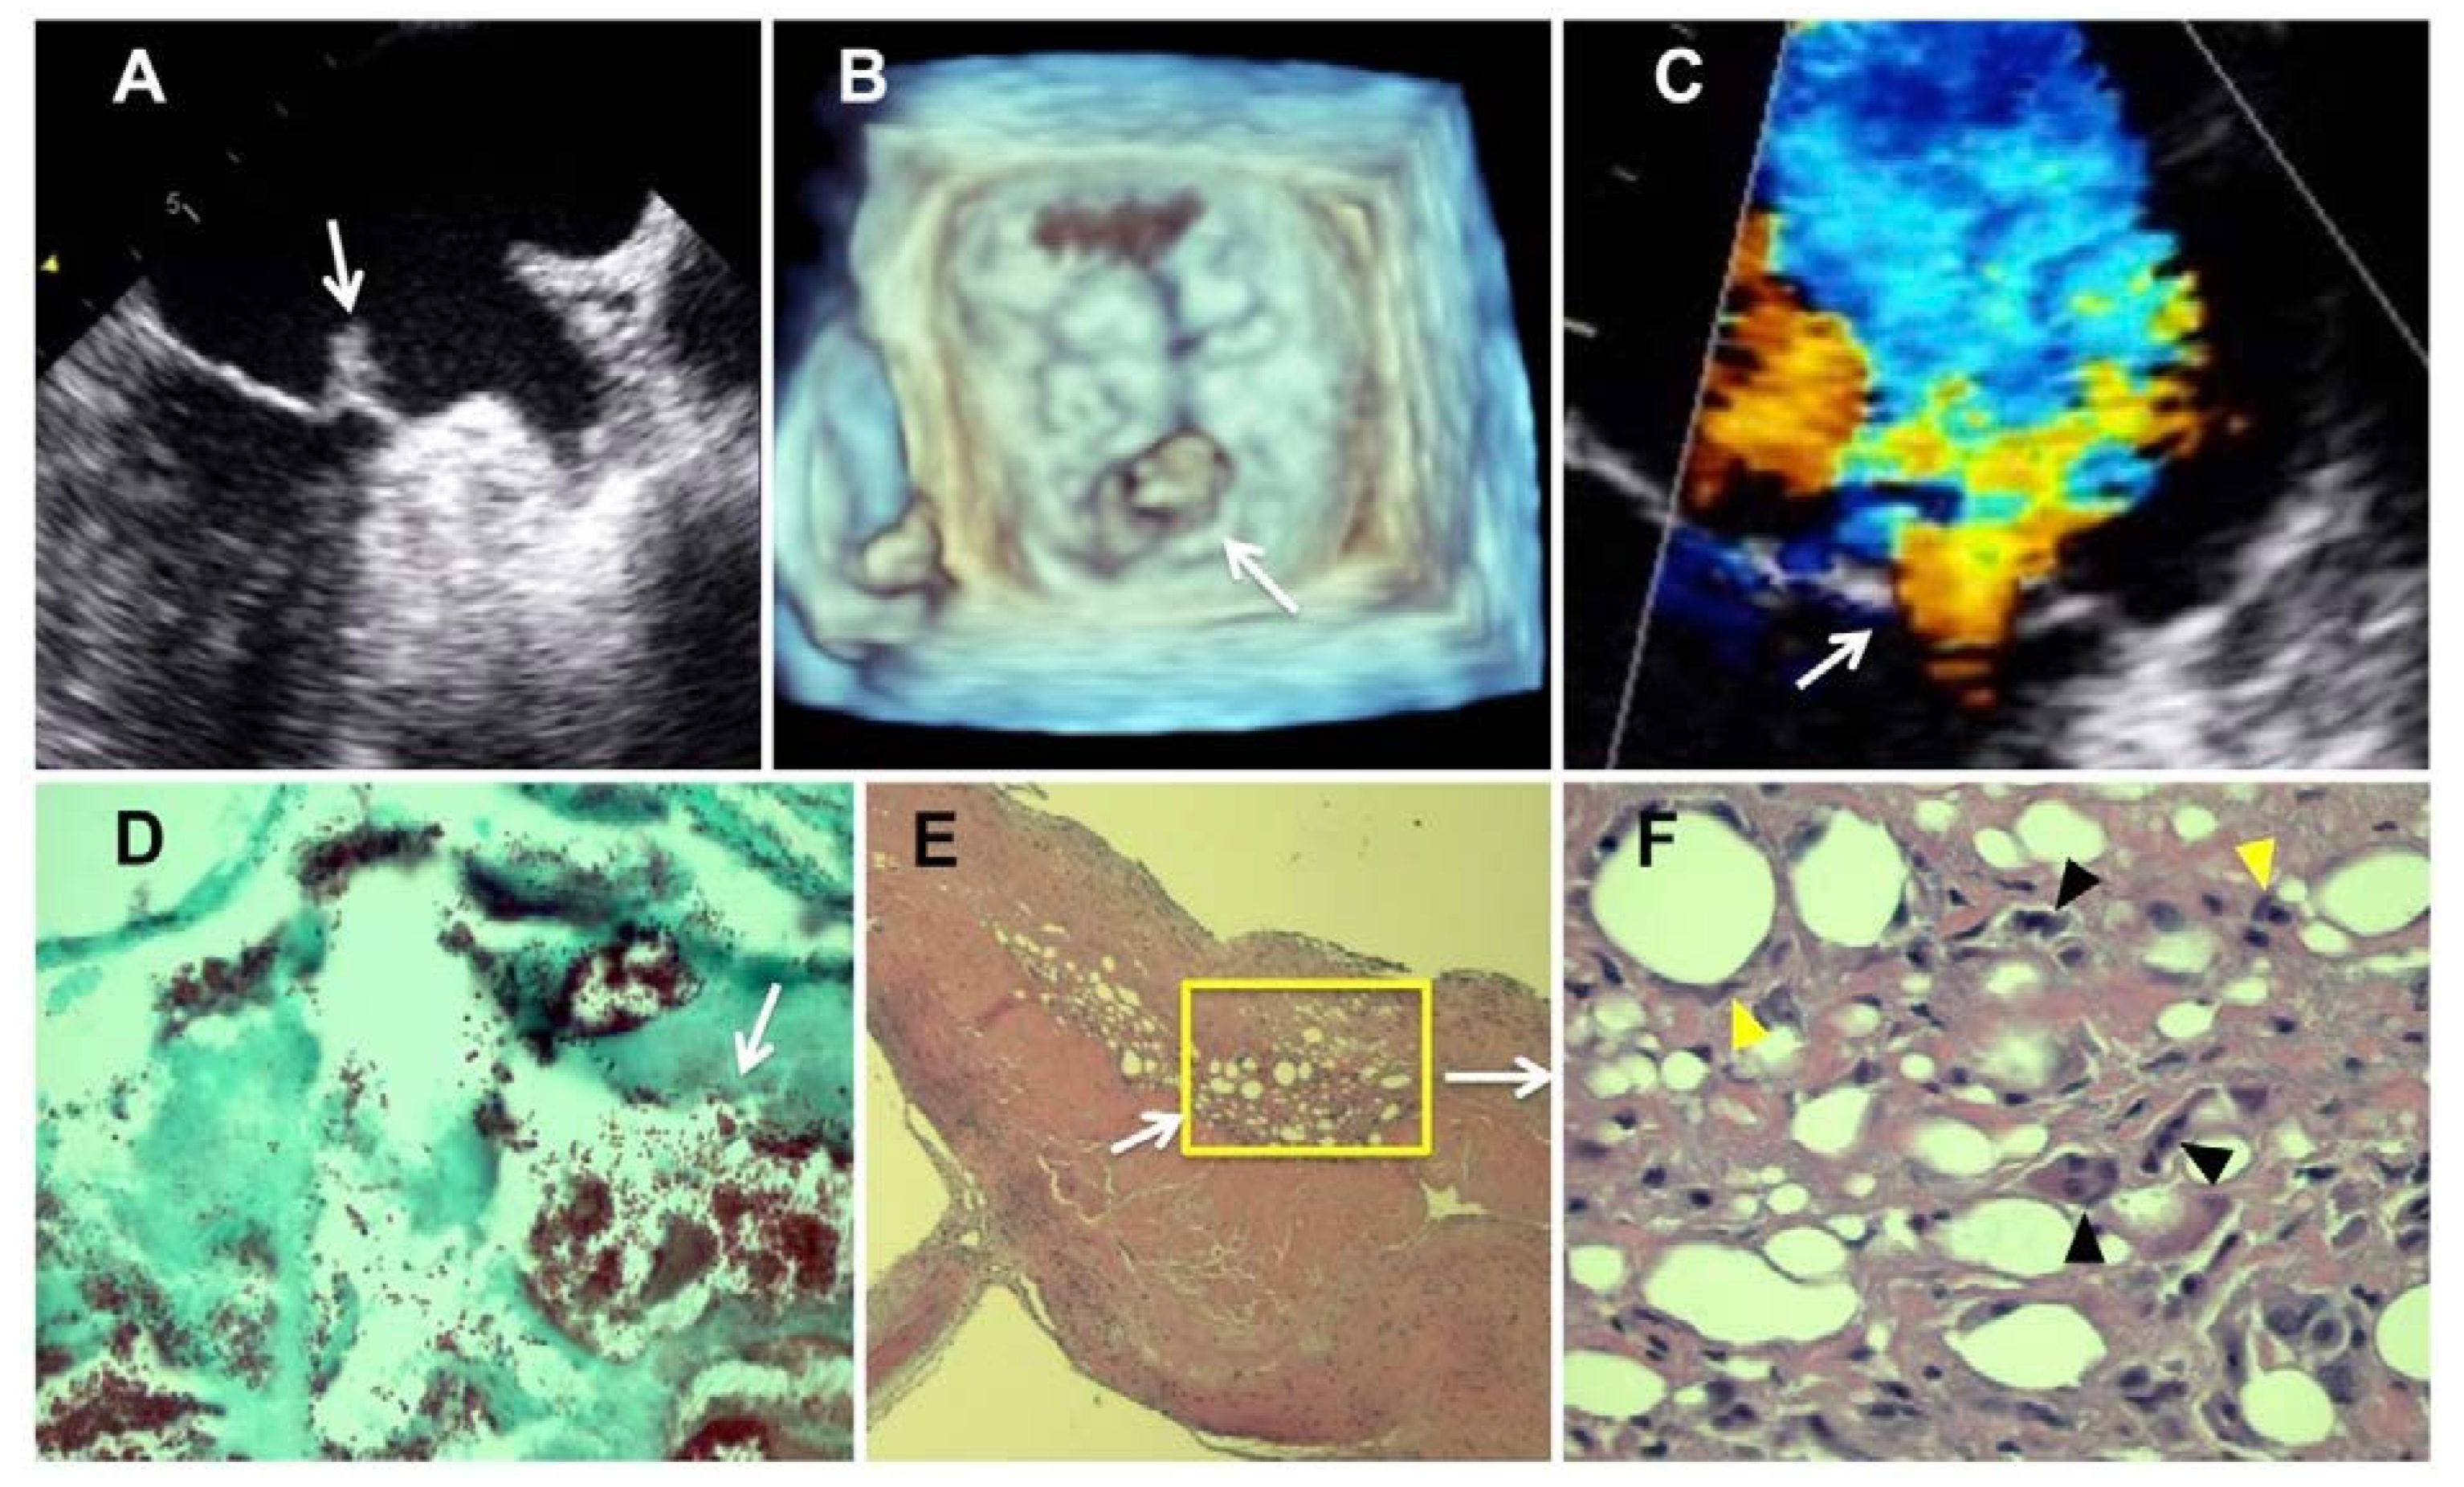

He was admitted with a diagnosis of congestive heart failure with mitral regurgitation and atrial fibrillation. Admission labs included a complete blood count with normocytic anemia (hemoglobin 11.2 g/dL, mean corpuscular volume 82 fL) and a comprehensive metabolic panel with an elevated but stable serum creatinine (1.54 mg/dL, creatinine clearance 57 mL/min). Urinalysis was positive for nitrite with moderate leukocytes and trace blood, and the patient was started on oral ciprofloxacin 250 mg every 12 hours for a possible urinary tract infection. Serum troponin I was normal. A transthoracic echocardiogram showed severe mitral regurgitation with normal left ventricular size and function (65%). A subsequent two-and three-dimensional transesophageal echocardiogram revealed a large, highly mobile vegetation (9.6 × 6.9 mm) on the atrial surface of the anterior mitral leaflet with aneurysmal destruction of the lateral scallop (Figure 1A–C). Three sets of blood cultures were drawn, as infective endocarditis was the dominant differential diagnosis. However, the patient was afebrile at this time and these cultures were drawn 5 days after ciprofloxacin was started.

Figure 1.

(A–F). Two-(A) and three-(B) dimensional transesophageal echocardiogram showing aggregated vegetations (white arrow) on the atrial surface of the highly mobile anterior mitral leaflet with aneurysmal destruction of the lateral scallop leading to severe mitral regurgitation. (C) Color Doppler revealing severe mitral regurgitation that fills up almost the entire left atrial cavity. (D) Gram stain showing both single and clustered gram-positive cocci (white arrow) aggregated at the endocardial surface (1000×, oil). (E; 250×, F; 400×) Hematoxylin and eosin stain showing ovoid empty spaces marginated by macrophages (yellow arrowheads) and Langhans giant cells (black arrowheads).

The resected valvular specimen showed gram-positive cocci (Figure 1D) surrounded by macrophages and Langerhans giant cells, aggregated at the endocardial surface. The histopathology showed interstitial gas consistent with pneumatosis (Figure 1E,F). His blood cultures remained negative, likely due to their collection post ciprofloxacin administration. Sequencing by PCR revealed the organism to be Enterococcus faecalis. The histopathological examination of the valve leaflet did not show signs of myxomatous degeneration. A diagnosis of emphysematous Enterococcus faecalis endocarditis of the mitral valve was made (Figure 2). Following mitral valve replacement, the patient was treated with 2 grams of intravenous ampicillin every 6 hours and 2 grams of intravenous ceftriaxone every 12 hours for six weeks and the patient’s condition improved. The patient’s post-operative course was notable for requiring intravenous hemodynamic support until post-operative day 4. He also required BiPAP and high flow nasal canula. A post-operative echo showed no acute changes. He underwent a peripherally inserted central catheter (PICC) line placement on post-operative day 5 for prolonged ampicillin and ceftriaxone administration. The patient was stable for discharge on post-operative day 10 and sent home on aspirin 325 mg daily, atorvastatin 40 mg daily, metoprolol 25 mg twice daily, furosemide 40 mg twice daily, and ampicillin and ceftriaxone as aforementioned. The patient was advised to follow up with cardiology, nephrology, and infectious disease and has not had further complications in over five years.

Two recognizable pieces of tan-yellow, pliable mitral valve leaflets were received in formalin fixative. The larger, 4.6 cm × 2.5 cm × 0.3 cm, bore numerous 1.5-2.5 cm thread-like 0.2 cm chorda tendineae. Several 0.25-0.5 cm soft, pink-tan elevations grossly resembling infective vegetations were scattered on the atrial surface of the valve leaflet. Similar vegetations were present near the insertional ends of some of the chorda tendineae. A grossly unremarkable, 1.75 cm × 2 cm × 0.3 cm, piece of mitral valve leaflet which bore a single chorda tendineae was also submitted (Figure 2). Microscopically, numerous single and clustered gram-positive cocci were present within the fibrinous vegetations and the immediate subjacent matrix of the mitral leaflet. Within the latter, conspicuous ovoid empty spaces were marginated by macrophages and Langerhans giant cells (Figure 1D). We recognize the difficulty in distinguishing interstitial gas from lipid; however, the empty spaces were devoid of the signet ring of cytoplasm and solitary nucleus which would categorize adipocytes. Neither foam cells, formation of granulomata, nor degenerating adipocytes were identified. In this setting of acute bacterial endocarditis due to a gas-forming organism, absence of intact and degenerating adipocytes, and the macrophage and giant cell reaction at the edges of the empty spaces (well-documented in the gas spaces of pneumatosis cystoides intestinalis), the diagnosis of emphysematous endocarditis in our patient was supported (Figure 1E,F).